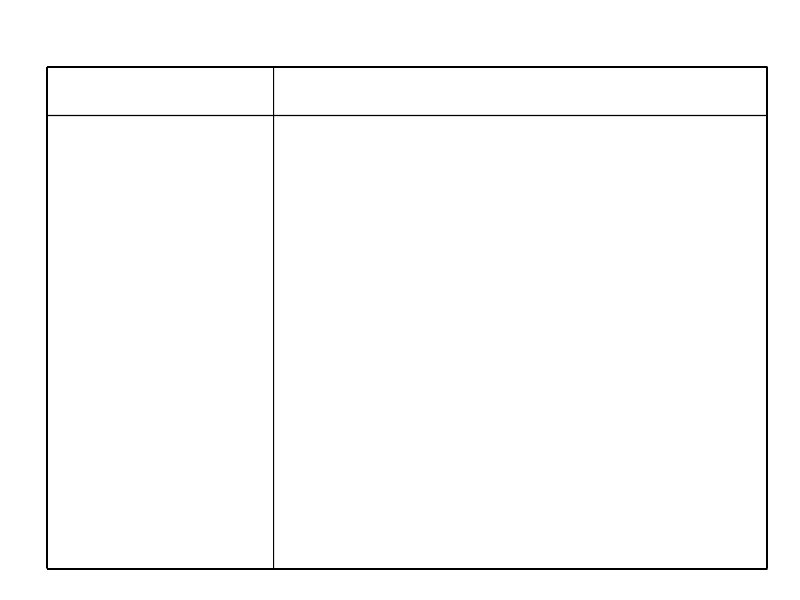

Тактика лечения больных ХЛЛ на постремиссионном этапе